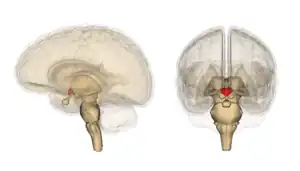

Hypothalamus

• Hypothalamus. Medulla: dorsal nuc. of vagus. - Autonomic dysfunction: temperature; cardiocirculatory; respiratory.

Lesions are usually symmetrical in the periventricular region, diencephalon, the midbrain, hypothalamus, and cerebellar vermis. Brainstem lesions may include cranial nerve III, IV, VI and VIII nuclei, the medial thalamic nuclei, and the dorsal nucleus of the vagus nerve. Oedema may be found in the regions surrounding the third ventricle, and fourth ventricle, also appearing petechiae and small hemorrhages.[52] Chronic cases can present the atrophy of the mammillary bodies.[53]